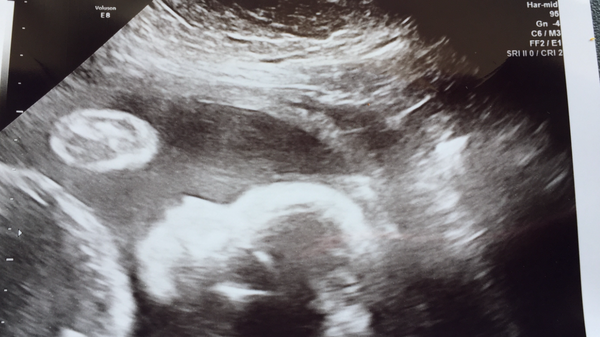

Blondes - good luck tomoz! 20w scan went well. Front placenta and slightly awkward bubs mean we go back in 2w to check the heart (only visible laterally today).

Tea. Glad scan went well tho naughty baby not showing all. Mine was the same. Took 3 attempts to get all measurements and sex

Next scan is the second shat at heart and thorax for anomaly - will be at 22 weeks then. I'll ask! Ta.

Is baby teaspoon not being helpful?

Bubs was the same. Took 3 attempts to get all measurements